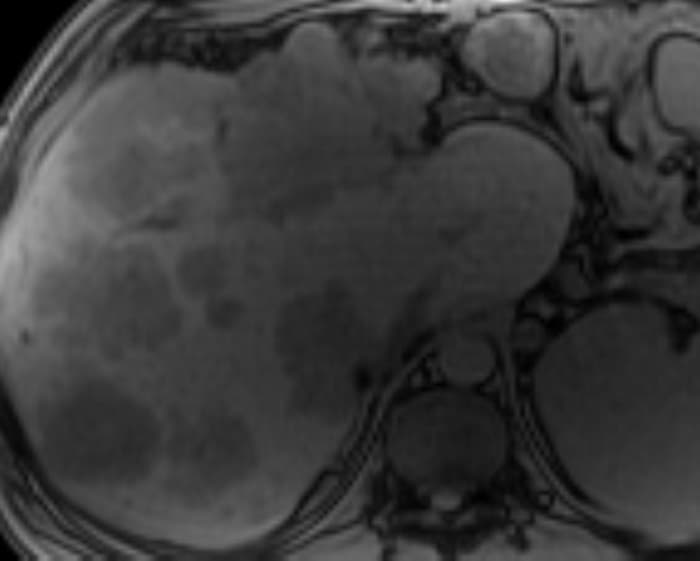

Di căn gan

» Thông tin: Nam giới – 37 tuổi.

» Lâm sàng: Tiền sử K đại tràng.